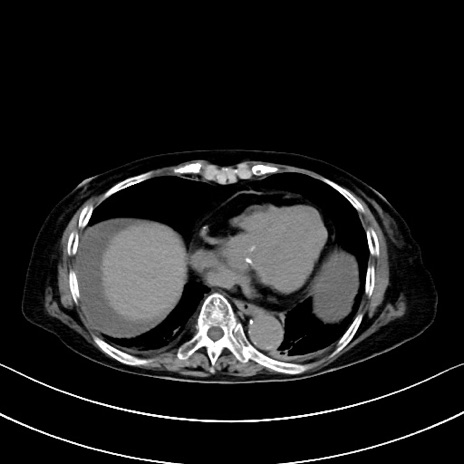

症例40(横断像)他院1日前

横断像

他院CT